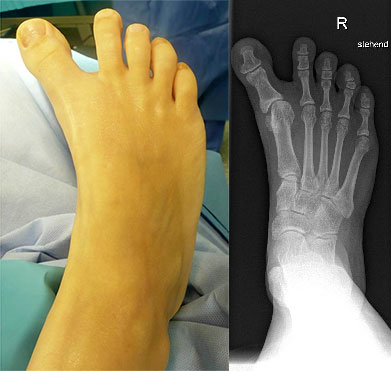

Klinisches Erscheinungsbild eines Hallux varus (eigenes Bildmaterial)

Abbildung 1

Radiologische Diagnostik

11"> Der Hallux varus Winkel  <a class=11" title="Der Hallux varus Winkel 11" srcset="/assets/images/2/4-vk3bypbg5s5x7zc.jpg 1x, /assets/images/3/4-aax2sd1hrpnrvrb.jpg 1.452x" width="270" height="240" loading="lazy">

Abbildung 3

Die bildgebende Diagnostik hilft bei der Klärung der Ätiologie und des Ausmaßes der Fehlstellung. Hierzu sind Röntgen­aufnahmen im Stand in mindestens zwei Ebenen unter Belastung des Fußes erforderlich. Mit Hilfe der belasteten Röntgenaufnahmen wird der Hallux-varus-Winkel, d. h. den Winkel zwischen der Achse der Grundphalanx der Großzehe und der Achse des ersten Mittelfußknochens bestimmt, sowie etwaige Rotationsfehlstellungen des 1. Strahls verifiziert. Eventuelle knöcherne Fehlanlagen bei kongenitalen Deformitäten können hierdurch ebenfalls verifiziert werden.